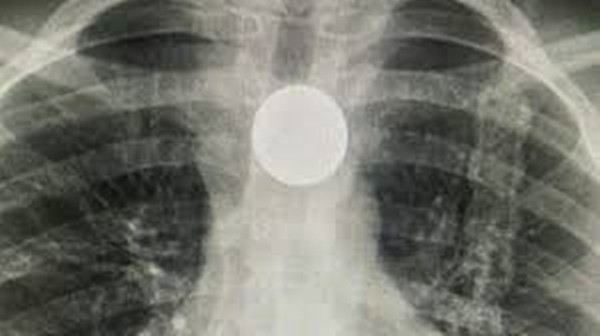

Bố mẹ cô bé lập tức đưa con vào bệnh viện. Bố Dhakota nói: “Tôi đã không biết là tình hình tệ đến mức nào, cho tới lúc bác sĩ cho xem phim chụp X-quang. Đồng xu đang mắc ở thực quản của con bé”.